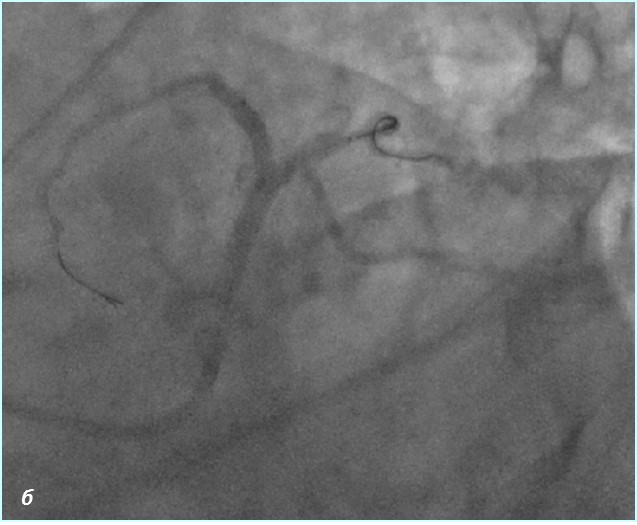

До проведения реваскуляризации миокарда пациент получал двойную антиагрегантную терапию (клопидогрел 75 мг, ацетилсалициловая кислота - 300 мг ежедневно). Чрескожное коронарное вмешательство было разделено на два этапа. Первым этапом – планировалось выполнить реканализацию и стентирование ПМЖВ, вторым – стентирование ПКА. Однако по данным повторной коронарографии было выявлено сужение тела ствола левой коронарной артерии (ЛКА) на 30%, окклюзия от устья передней межжелудочковой артерии (ПМЖВ), постокклюзионный сегмент заполнялся по слабым внутри- и межсистемным коллатералям, устьевое сужение огибающей артерии (ОВ) 60%, окклюзия средней трети правой коронарной артерии (ПКА), постокклюзионный сегмент заполнялся по внутрисистемным перетокам. Показатель Syntax Score для данного пациента составил 34.5. Учитывая, что по данным ранее выполненной коронарографии, правая коронарная артерия оставалась проходимой, а передняя межжелудочковая ветвь была окклюзирована и на момент реваскуляризации срок окклюзии составлял 7 лет, была проведена сменена тактики и первым этапом выполнена реканализация правой коронарной артерии, а спустя 2 суток – реканализация и стентирование передней межжелудочковой ветви от устья с баллонной ангиопластикой огибающей ветви (рис.1,2). Учитывая, что проводилась реканализация хронической окклюзии, в обе коронарные артерии были имплантированы стенты с лекарственным покрытием Resolute ONYX (Medtronic).

Рис.2 Ангиограмма левой коронарной артерии. а) при коронарографии левой коронарной артерии –артерия окклюзирована от устья (стрелка); б) проходимость по левой коронарной артерии полностью восстановлена